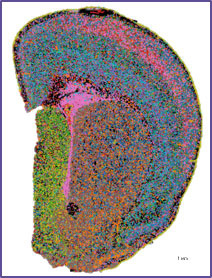

空間解析結果をStereoMapというソフトウェアで可視化した結果をお示しします。部位特異性の高い遺伝子を一覧、それぞれの発現パターンを組織のイメージと重ね合わせて可視化することが可能です。

例えば、滑脳症の原因遺伝子とされているαチューブリンの遺伝子は主に皮質部分で発現、家族性アミロイドポリニューロパチー (FAP) への関連が示唆されているトランスサイレチン遺伝子は、海馬付近で特異的に発現していることが観察できます。

部位特異性の高い順に記載